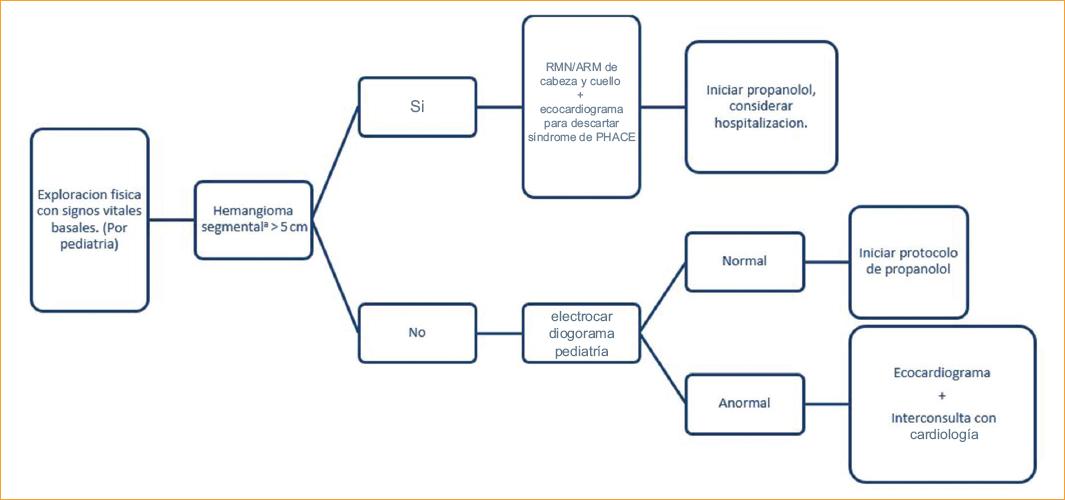

Haider, et al. publicaron en 2010 un protocolo para el tratamiento con propanolol oral sin la necesidad de hospitalización (Fig. 4) en 17 pacientes, y lograron detener el crecimiento o disminuir el tamaño de todas las lesiones tratadas. Solamente se presentaron efectos secundarios, que fueron leves, en 6 de estos pacientes, y no hubo necesidad de suspender el tratamiento en ningún paciente17(Tabla 1).

Figura 4 Protocolo para la evaluación de pacientes previos al tratamiento con propanolol (modificado de Haider, et al.16).aLesión lobulada con configuración geográfica.PHACE: malformaciones cerebrales de la fosa Posterior, Hemangiomas, anomalías Arteriales, Coartación de la aorta y defectos cardíacos, y anormalidades oculares (Eye abnormalities); RMN: resonancia magnética nuclear.